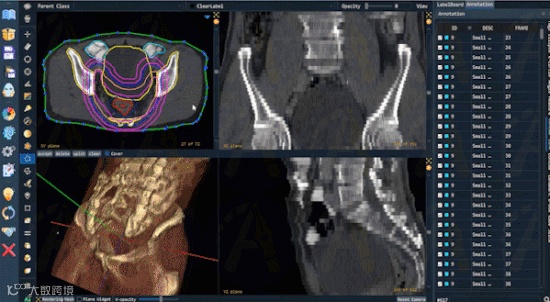

支持放疗勾画的DICOM RT Struct

鉴于放射科对AI研究的重大需求,Pair新增了对放射影像DICOM RT Structure文件格式的全面支持。放射科医生将TPS (Treatment Planning System)放疗规划系统中勾画的放疗靶区轮廓线以RT Struct格式导出后,可直接在Pair中打开,进行可视化和进一步的标注优化。Pair可支持超1000条RT轮廓线的标注交互。Pair更可以将RT Struct内的轮廓线填充并导出成分割标注结果文件,如nii, nii.gz等格式,极大地方便放射科医生使用专业的影像组学软件,如TexRAD、MaZda等,进行后续的高阶分析与研究。